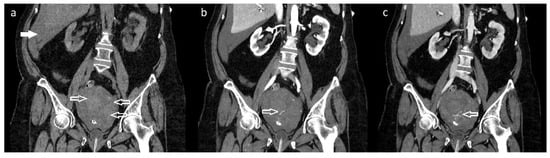

Figure 1. Abdominal computed tomography (CT) scan with the application of 90 mL intravenous contrast medium Visipaque 320 revealed a uterine tumor involving the cervix (size: 40 × 50 × 70 mm), hematometra with active bleeding from the tumorous mass, and a hemoperitoneum. (a) Non-contrast: coronal plane with hematometra in the enlarged uterus with tumor (arrows) and hemoperitoneum located in the Morison’s pouch (full arrow). (b) Contrast enhanced: coronal plane (arterial phase 30 s after applying the contrast agent) where an active extravasation of the contrast agent from the dorsocaudal part of the tumor can be seen (arrow). (c) Contrast enhanced: coronal plane (venous phase 70 s after applying the contrast agent). Continued process of the extravasation of the contrast agent, pointing to actively bleeding arterial area (arrow). A 67-year-old patient was referred to our department with a sudden onset of sharp lower abdominal pain and an episode of vaginal bleeding. The patient had a short history of intermittent, low-intensity postmenopausal bleeding and the diagnosis of pelvic mass on the ultrasound (although the diagnostic process for this was incomplete). Upon admission the patient had tachypnea, tachycardia, and diffuse abdominal rigidity. A speculum vaginal examination showed a small and extremely hard to visualize portion of ectocervix and, by bimanual palpation, a tumorous mass (involving both cervix and parametria) was diagnosed (minimal vaginal bleeding present). An urgent computed tomography scan was ordered which revealed an enlarged uterus with a tumor in the cervical region and active extravasation in the arterial and venous phase after applying the contrast, which pointed to active arterial bleeding from the lesion causing hematometra and subsequently uterine rupture and hemoperitoneum. We considered an acute surgical intervention as an unfavorable option because it was a locally advanced disease which had altered the pelvic anatomy in an already hemodynamically unstable patient. There was also a significant drop in hemoglobin levels (123 g/L vs. 100 g/L samples taken in approximately 1.5 h interval), which pointed to a major blood loss. We were informed about the possibility of a UAE and, after the required initial management and blood transfusions, the patient was transported to the angiography department.